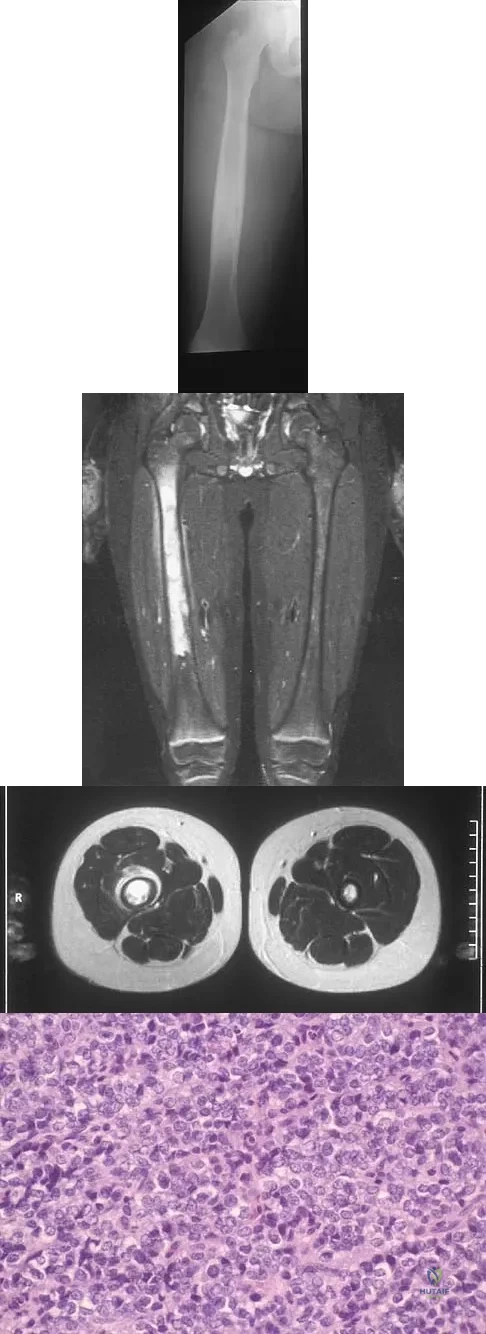

A radiograph, MRI scans, and a biopsy specimen of a 9-year-old boy with thigh pain are shown in Figures 37a through 37d. Management should consist of

Explanation